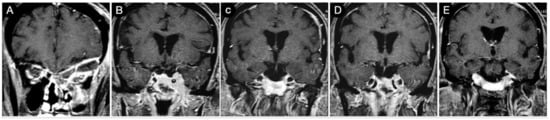

Case #1: Infradiaphragmantic Tumor with Middle Fossa Involvement through the Cavernous Sinus